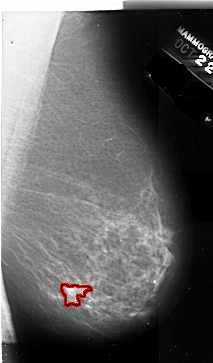

A_1008_1.RIGHT_CC

RIGHT_CC LINES 6511 PIXELS_PER_LINE 3721 BITS_PER_PIXEL 16 RESOLUTION 42 OVERLAY

FILE: A_1008_1.RIGHT_CC.OVERLAY

TOTAL_ABNORMALITIES 1

ABNORMALITY 1

LESION_TYPE MASS SHAPE IRREGULAR MARGINS ILL_DEFINED

ASSESSMENT 4

SUBTLETY 4

PATHOLOGY MALIGNANT

TOTAL_OUTLINES 1

BOUNDARY